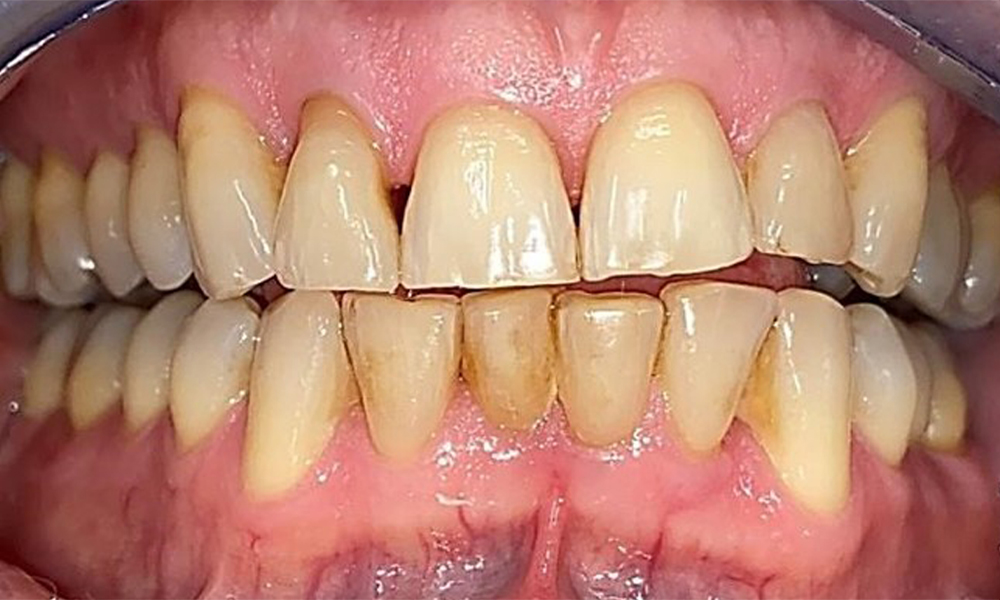

Right lateral view. Loss of the interdental papillae.

Fig. 3 Right lateral view. Loss of the interdental papillae. © Dr R. Krapf

The patient has stage II, grade B periodontitis (5). At 1 to 3 mm, the clinical probing depths were within the physiological range. Localized probing depths of 5 mm were observed on the mesiopalatal aspects on both 17 and 27. There are generalized recessions of 1–3 mm with partial loss of the interdental papillae (Fig. 2, Fig. 3, Fig. 4)